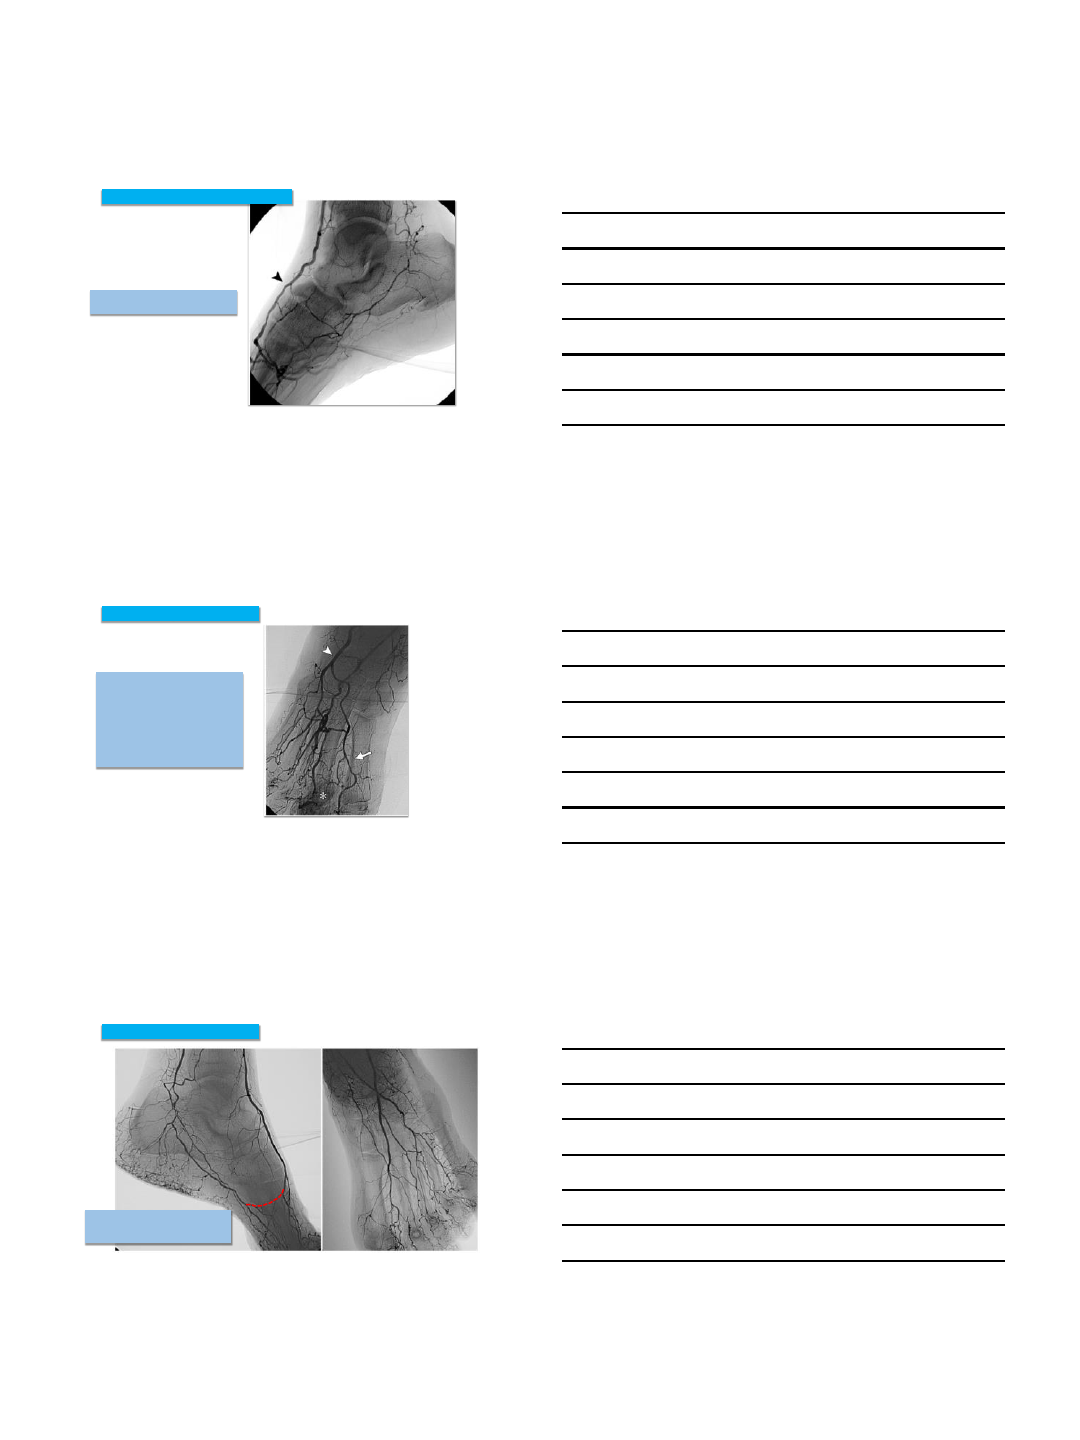

Anterior circulation is occluded and the

medial plantar provides sole pedal

blood flow.

Medial Plantar fills Lateral Tarsal

and anterior pedal circulation

Pedal Plantar Loop: Connections and Collaterals

Manzi et al. RadioG raphics 2011; 31:1623–1636

Posterior circulation is occluded but

fills from anterior circulation

Anatomic variation:

No dorsalis pedis: Lateral tarsal

artery is the dominant anterior

vessel: 6-12% individuals.

The arcuate artery which normally

originates from the dorsalis pedis is

missing: ~ 30% of individuals.

Pedal Plantar Loop: Anatomic Variation